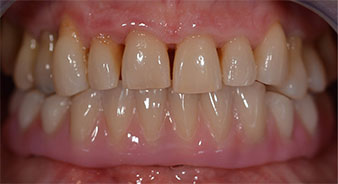

След това е взет отпечатък и е определена захапката на пациента, за да може зъботехникът незабавно да започне изработването на временната протеза. Протезата е поставена в същия ден (Фиг. 17 и 18).

Импланти

Фиг. 17

Фиг. 18

След изчакване на необходимото време за осеоинтеграция, финалният отпечатък на имплантите е свален и следователно е изработена финалната протеза (Фиг. 19 и 20). В този момент, лекарят по дентална медицина и пациентът могат да обсъдят дали да използват керамични или пластмасови фасети и циркониева или метална рамка. В този случай, екипът на д-р Паску избира пластмасови фасети, имайки предвид неясната прогноза относно частичното обеззъбяване в челюстта и фактът, че зъб 24 е прорастнал. Този вид протеза обикновено е по-лесна за адаптиране и впоследствие може да бъде променяна спрямо новата ситуация в челюстта.